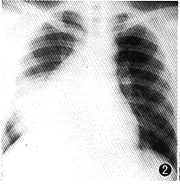

例2 患者男,22岁。因胸闷气促,右胸痛,咳嗽2月于1999年7月2日入院。入院体检:一般情况差,抬入病房,呼吸急促,神志清,唇无紫绀,颈静脉无怒张,心率115次/min,律齐,右侧呼吸运动较左侧降低,右肺语颤较左侧减弱,叩诊呈浊音,呼吸音明显减轻,左肺呼吸音粗,未闻及音。腹部未见异常,双下肢无水肿。血白细胞8.4×109/L,中性0.66,淋巴0.34,血红蛋白92 g/L,肝肾功能、电解质均正常。多次浓缩痰找抗酸杆菌及痰脱落细胞检查均阴性。心电图示窦性心动过速。动脉血气分析在正常范围。B超示右胸腔中等量积液。腹、脑CT均未见异常。胸部X线示右侧第一前肋以下至横膈有大片致密影,右侧肋膈角、横膈面消失,左侧未见病灶(图2)。胸部CT示右前纵隔见巨大类椭圆形软组织影,约13 cm×12 cm×16 cm,边缘毛糙分叶,僵硬感,其内密度不均,CT值为6.5 Hu~30.3 Hu,不规则增强,无钙化灶。右前胸壁肋间隙扩大,心影及大血管向左后推移,右上叶前段、中叶支气管受压,变窄,右侧胸腔见中等量积液,局部包裹伴结节,右下肺压缩,不张,左肺无病灶(图3)。于1999年7月9日行开胸手术。术中见肿瘤上达锁骨水平,下至横膈,上下径30 cm,左右径约5 cm,前后径25 cm,侵犯右侧心包范围达8 cm×8 cm。肿瘤呈分叶状,暗褐色,有弹性,并有局部液化,侵犯右下叶及中叶,故行右全肺加肿瘤切除术。病理标本见右全肺胸膜广泛粘连,肿块与下叶紧密相连,肿块约16 cm×9 cm×8 cm,红褐色,右全肺受压,萎缩。病理证实为右前纵隔恶性卵黄囊瘤,心包受侵。术后恢复良好,于7月29日出院。